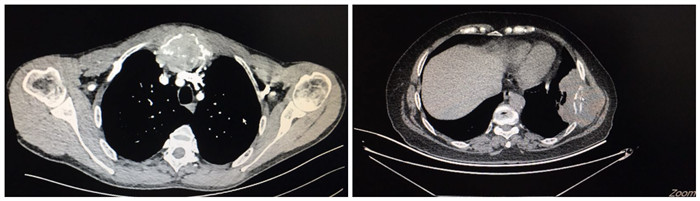

患者张先生,发现胸骨肿瘤4月,CT提示胸骨柄、胸肋关节软组织肿块,最大直径约8cm,考虑肿瘤性病变。另一患者 李女士,因发现肋骨肿瘤4月余入院,CT提示左侧7肋团块状软组织密度影,约8x5cm大小,边界不清,骨质破坏,突入胸腔。两例患者病情复杂,肿瘤巨大,家属均辗转求医来医院,强烈要求手术治疗。若行手术,不仅需完整切除胸骨、肋骨肿瘤及受累的相邻胸壁组织,还需要进行复杂的胸壁重建。西安交通大学第二附属医院胸外科主任李少民教授查看患者,分析影像资料后,决定为患者实施完整肿瘤切除并3D打印胸壁重建手术,经联系空军军医大学附属唐都医院胸外科黄立军教授,商讨制定手术方案,并组织科室骨干人员形成治疗小组。治疗团队分别根据患者胸骨肿瘤及肋骨肿瘤的侵及范围制定了严谨、详细的手术方案,并分别绘制两例患者需切除的胸壁缺损的范围,随后利用3D打印技术制作了高度契合患者缺损部位的PEEK材料胸骨及肋骨植入体。完善术前准备后,在黄立军教授团队协助下顺利完成了手术。

患者术前影像资料